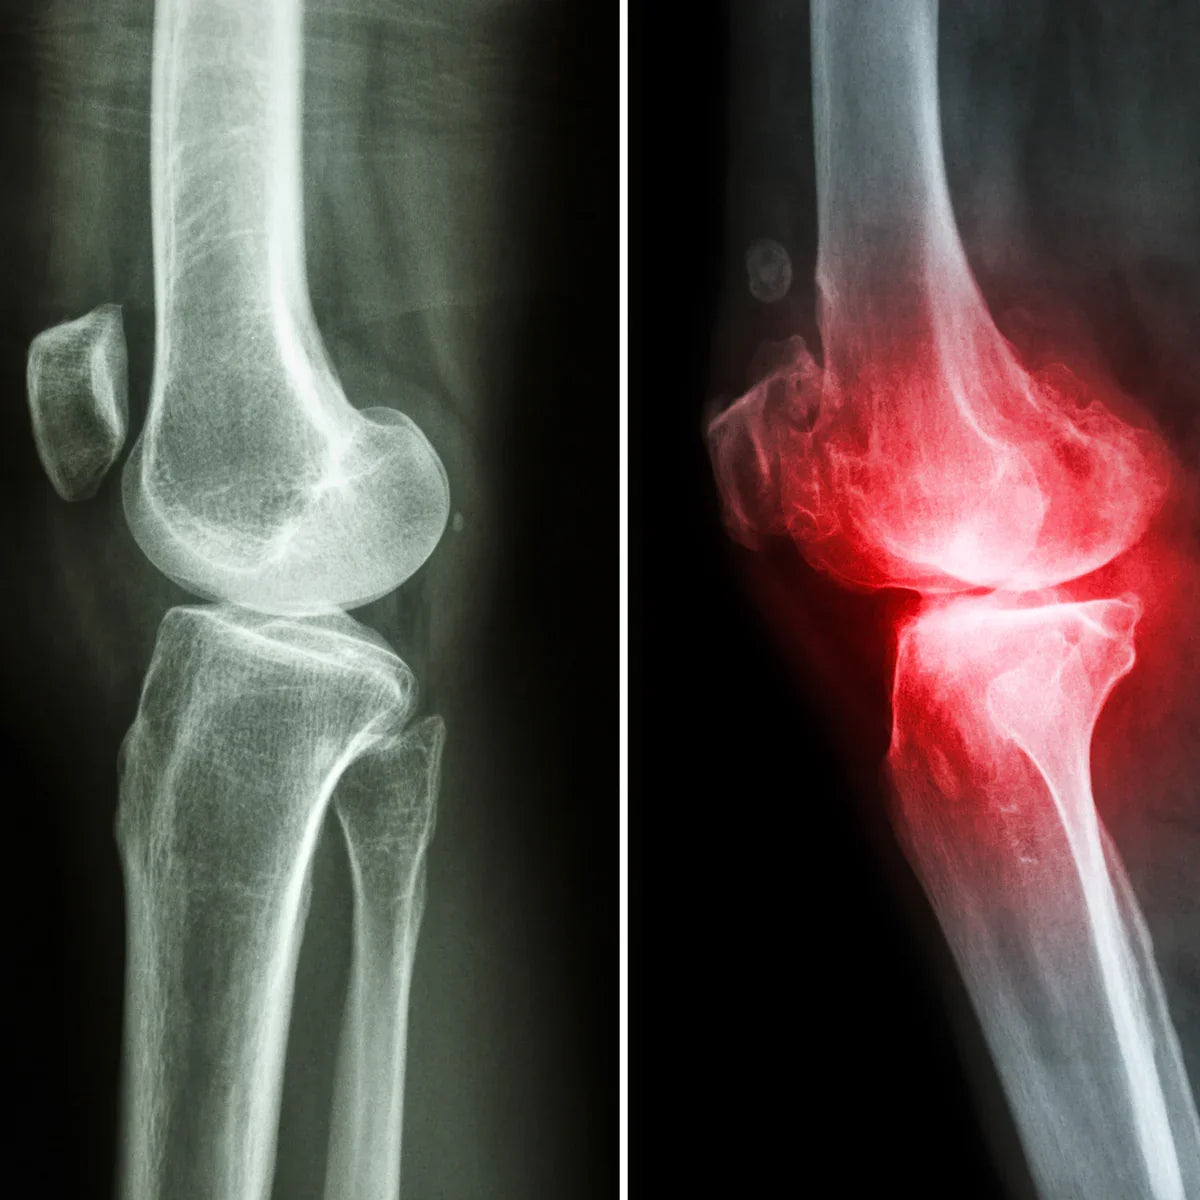

Arthro4 je kompleks za zmanjšanje vnetja sklepov in krepitev hrustanca z bioaktivnimi rastlinskimi sestavinami. Njegova glavna sestavina je novozelandska zelenousta školjka in vsebuje koncentrate učinkovin 3 najmočnejših naravnih zelišč za podporo sklepom in hrustancu: hudičeva kremplja, kurkuma in bosvelijev ekstrakt.

Zelene školjke so na podlagi raziskav in izkušenj ena najboljših snovi za regeneracijo in krepitev sklepov ter hrustanca. S svojim bioaktivnim glukozaminom neprestano obnavljajo telesni sistem za absorpcijo udarcev. [01.]

Njegova hranila pomagajo ohranjati gibljivost ter zdravje sklepov in hrustanca. Zelena školjka vsebuje tudi dve najpomembnejši Omega-3 maščobni kislini, DHA in EPA, ki imata močne protivnetne učinke. Zaradi tega sta še posebej koristni pri vnetju sklepov ali kakršni koli bolečini in nelagodju v mišično-skeletnem sistemu.

Naravne gradnike hrustanca, glukozamin sulfat in hondroitin sulfat, najdemo tudi tukaj. Ti prehranjujejo in krepijo sklepe ter povečujejo njihovo odpornost proti obrabi. Poleg tega podpirajo gradnjo glavnih strukturnih elementov hrustanca, zaradi česar so nepogrešljivi za ohranjanje in obnovo integritete sklepnega hrustanca.

Glukozamin je temeljni gradnik ligamentov in kit. Zavira določene encime, ki razgrajujejo hrustanec, s čimer upočasni ali ustavi razgradnjo hrustanca. Poleg tega izboljšuje viskoznost sinovialne tekočine ter ima močne protivnetne in protibolečinske lastnosti.

Zelena školjka vsebuje več kot 13 % glukozaminoglikana, zaradi česar je zelo učinkovita pri zagotavljanju gladkega, brez trenja delovanja sklepov. Posledično lahko odpravi vnetja v mišicah, kitah in sklepnih predelih ter celo regenerira poškodovana tkiva.

10 pogojev, kjer je njegova uporaba priporočena

| ✓ Osteoartritis |

| ✓ Revmatoidni artritis |

| ✓ Bolečine v hrbtu, bolečine v spodnjem delu hrbta |

| ✓ Bolečina v kolenu |

| ✓ Bolečina v rami |

| ✓ Fibromialgija |

| ✓ Lupus |

| ✓ Tenis komolec |

| ✓ Lumbago |

| ✓ Astma |

Glavna aktivna sestavina kurkume je kurkumin, močna spojina polifenolnega antioksidanta z učinkovitimi protivnetnimi, imunostimulativnimi in proti bolečinam delujočimi lastnostmi. Zaradi tega je kurkuma učinkovita proti vnetju sklepov, obrabi hrustanca in revmatološkim težavam.

Kurkumin zmanjšuje sintezo levkotrienov, vnetnih nevrotransmiterskih molekul.

Raziskave so pokazale, da kurkuma krepi hrustanec in spodbuja proizvodnjo kolagena, kar je bistveno za razvoj hrustanca. Tako kurkuma ščiti hrustanec pred razgradnjo, zmanjšuje vnetje in podpira nastajanje novega hrustanca. [02.]

Hudičeva kremplja je učinkovita protivnetna, proti oteklinam in protibolečinska snov. Uporablja se lahko pri kroničnih bolečinah v hrbtu, degenerativnih revmatoloških obolenjih, vnetjih kit (npr. teniški komolec), boleznih sklepov, obrabi hrustanca ali išiasu.

Številne raziskave so pokazale, da izvlečki hudičevega kremplja vodijo do zmanjšanja bolečine in izboljšane gibljivosti v nekaj tednih uporabe. Poleg tega so terapije s hudičevim krempljem na splošno dobro prenašane, stranski učinki pa se pojavljajo redko. [03.]

Hudičev krempelj je posebej koristen za revmatološki artritis (revmatološko vnetje) in boleče sklepe. Primeren je tudi za sproščanje in regeneracijo utrujenih, preobremenjenih mišic, obnovo gibljivosti ter lajšanje bolečin.

Po operacijah ali nesrečah pripomore k hitrejšemu okrevanju okončin. Zaradi svojih izjemno učinkovitih analgetičnih lastnosti lajša bolečine in omili simptome različnih težav, vključno z vnetjem sklepov, protinom, bolečinami v hrbtu in ledvenem delu ter mišičnimi bolečinami.

Kadilo ali boswellia se že stoletja uporablja za protivnetne, protibolečinske in protirevmatične namene.

obraba hrustanca je posledica degeneracije hrustanca, ki ščiti sklepe. Raziskave kažejo, da bosvelija pomaga preprečiti to poškodbo v sklepnih tkivih in hrustancu. [04.]

Boswellia nudi izjemne protivnetne učinke, podobne nesteroidnim protivnetnim zdravilom, vendar ne draži želodčne sluznice.

Boswellia serrata:

- Lahko regenerira obrabljeni hrustanec in podpira regeneracijo hrustanca.

- Lahko pomaga pri okrevanju po herniranih diskih.

- Primerno za zdravljenje vnetja kosti in sklepov, osteoartritisa in revmatoidnega artritisa zaradi svojih protivnetnih učinkov.

- Njegove odlične protibolečinske lastnosti pomagajo lajšati artritične bolečine, bolečine v sklepih ter kronične bolečine v hrbtu in mišicah.

- Izboljša prekrvavitev vnetih sklepov, poveča gibljivost in upočasni razgradnjo sklepnega tkiva.

- Zmanjšuje oteklino in lajša bolečino pri bolnikih z vnetjem sklepov.

- Podpira krvni obtok v mišičnih tkivih in prispeva k utrjevanju hrustanca.

Mišično-skeletni sistemBolečine v sklepih • Osteoartritis • Revmatoidni artritis • Artritis kolčnega sklepa • Tenis komolec • Po poškodbi kolena • Bolečina v rami • Fibromialgija • Po zlomu kosti • Spondiloza